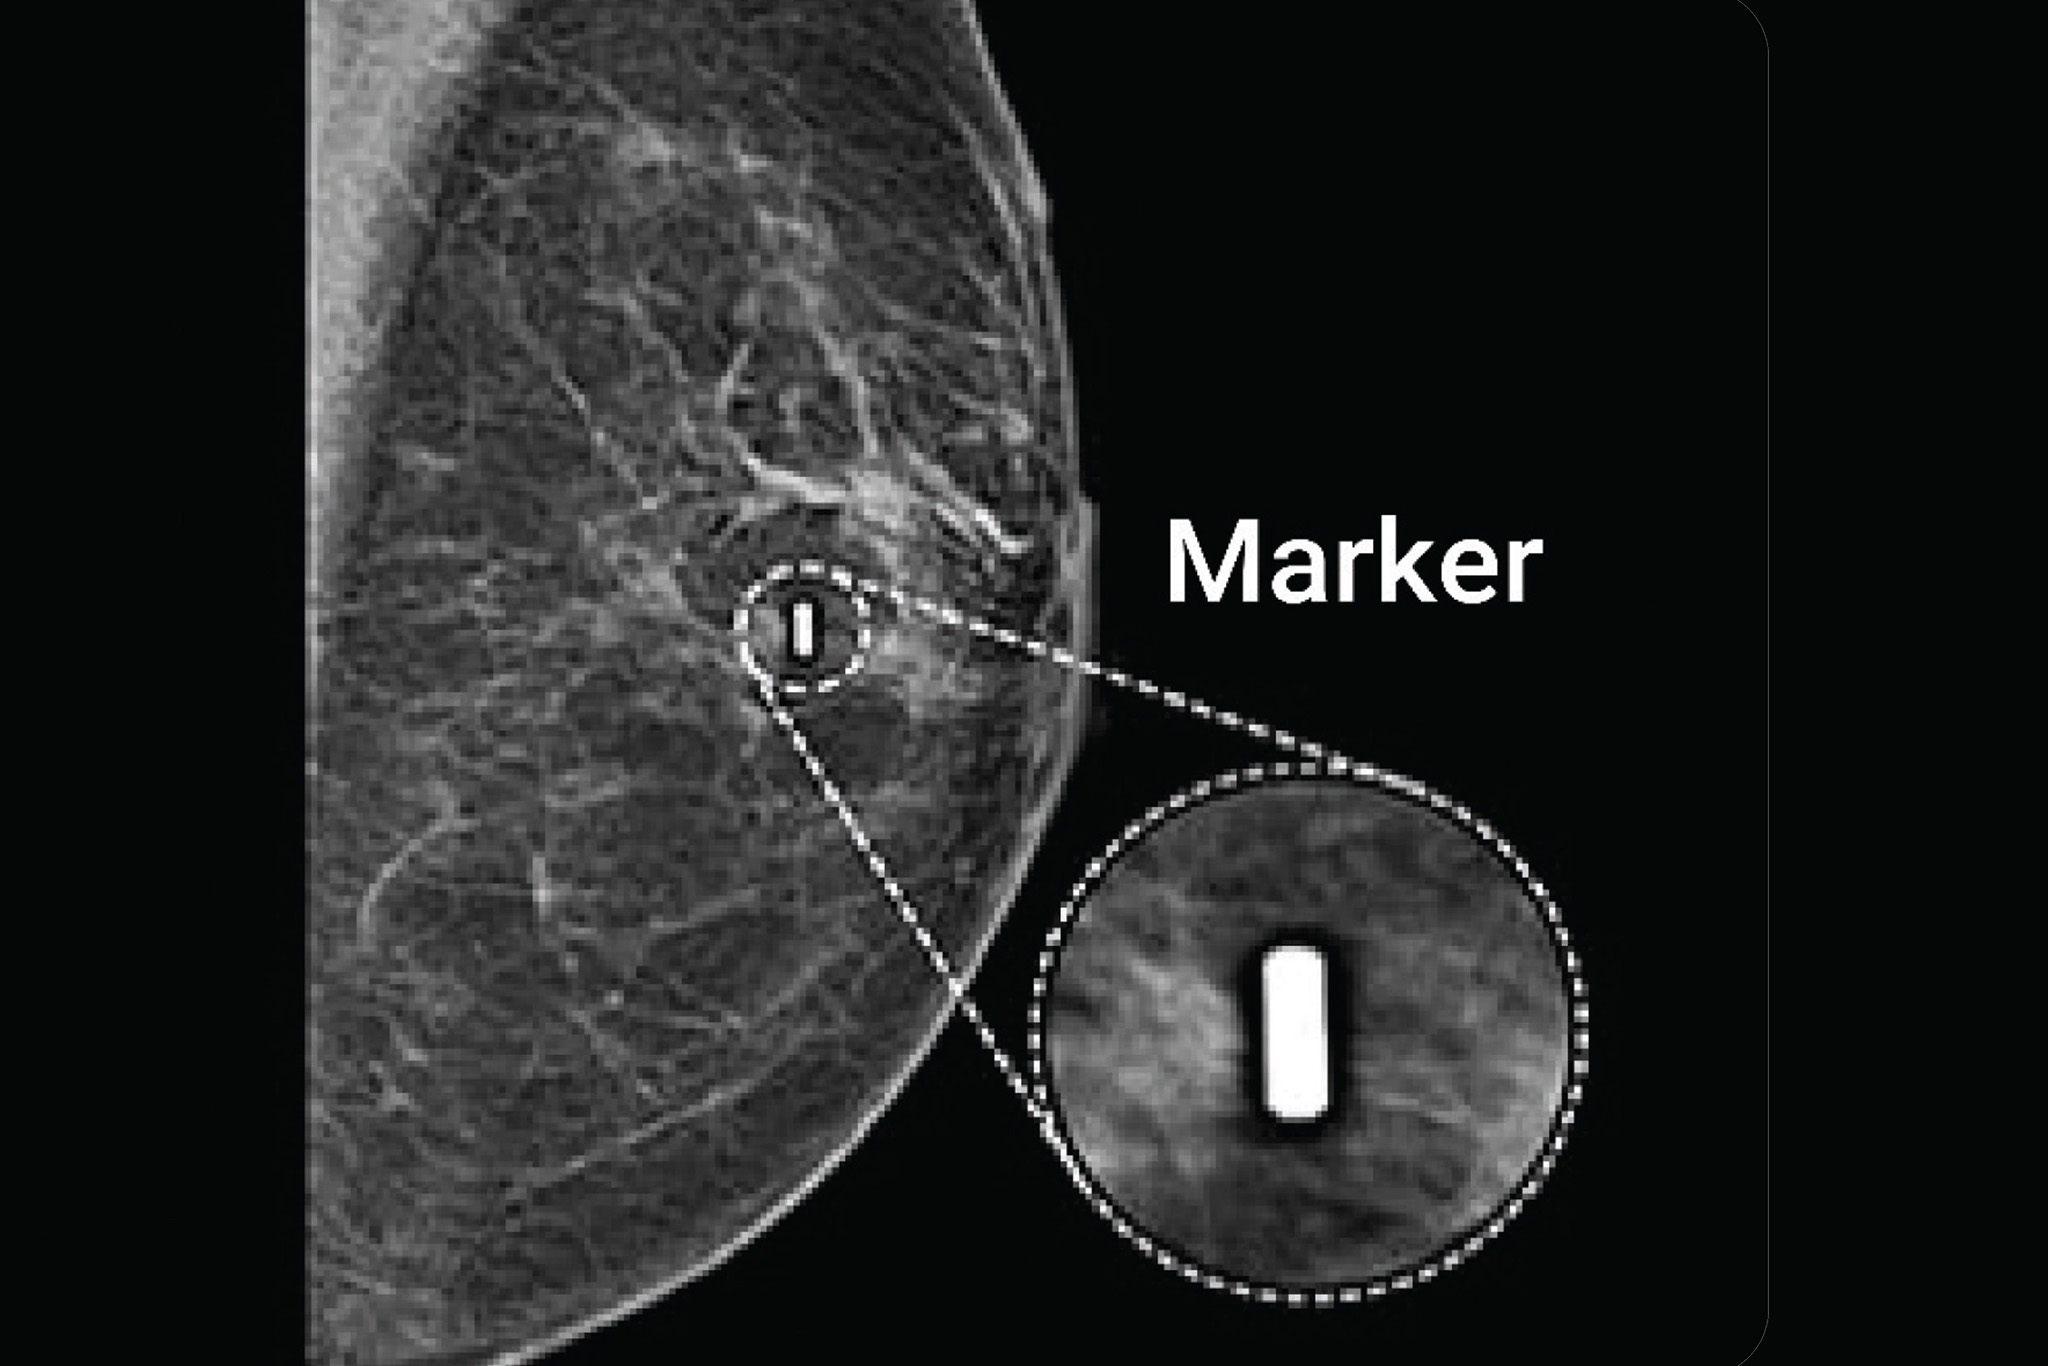

Breast Markers in Breast Cancer Care: Types, Placement and Clinical Use